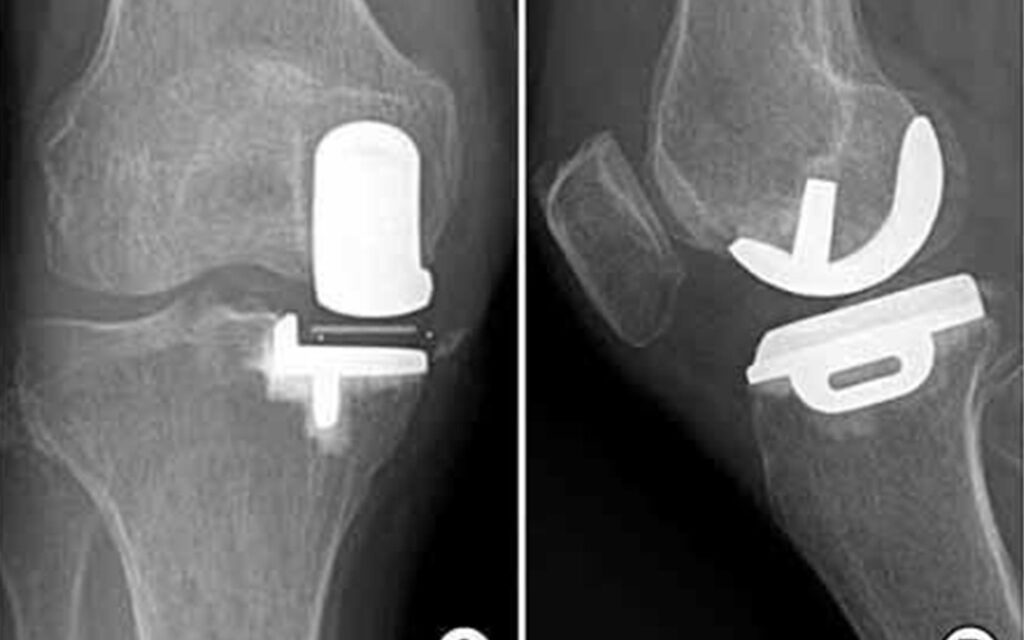

Pain in the knees is a common complaint that is experienced by individuals due to arthritis, injuries or wear and tear. Once medicine or other interventions such as physical therapy and lifestyle changes stop working, knee replacements are the best solution. Patients today in Mumbai now have the option of choosing between traditional knee replacement and newer optional robotic knee replacement surgery in Mumbai. Both are designed to relieve discomfort and restore movement, although there are substantial differences in accuracy, recovery and long-term outcomes. At Kneebotics, our Mumbai consultants utilise robotics for superior patient care. If you are wondering about robotic vs traditional surgery, let this guide explain the differences to you so that you can make an informed decision. What is traditional knee replacement surgery? Traditional knee replacement surgery requires the surgeon to physically remove your bone and cartilage from the knee joint, and replace it with an artificial implant. This operation has been reliably performed for seventy years, helping millions of patients to regain a working limb. This procedure is effective, but it depends upon the skill of the surgeon. Despite best judgments, minor misalignments are prone to happen, which could lead to implant failure in the long run. The more invasive procedure may also be associated with a longer recuperating time. What is Robotic Knee Replacement Surgery? Mumbai Knee Robotic Knee Replacement is the future of joint replacement! In this sophisticated technique, surgeons employ the assistance of robotic technology to meticulously prepare and perform the surgery. The process begins with a 3D CT scan of the patient’s knee to produce a virtual model. The robot system then assists the surgeon during the surgery procedure to position implants with a sub-millimeter accuracy. Despite popular misconceptions, the robot is not operating; rather, the robot serves as an extension of the surgeon’s hands, with real-time visual feedback. This state-of-the-art technology minimizes mistakes, safeguards surrounding structures, and allows for an individualized treatment for each patient. Robotic Knee Replacement vs Conventional Surgery – Key Comparisons Precision and Accuracy Conventional Surgery: In this technique, the implantation site is decided based on manual measurements and experience of the surgeon. Robotic Surgery Integration of advanced imaging and robotic guidance for precise alignment and positioning of the implant. Invasiveness of the Procedure Open Surgery: Large incisions and increased flesh damage. Robotic Surgery Minimally invasive with smaller incisions for less scarring and less blood loss. Recovery and Rehabilitation Conventional Surgery: It may also have longer recovery periods and a greater chance of stiffness and pain. Robotic Surgery: With speedier recovery time, less discomfort and an earlier resumption of walking and routine activities. Long-Term Outcomes Conventional Operation: High success rates, but depends on the experience of the surgeon. Malalignment can occasionally cause it to loosen, requiring you to have another operation. Robotic Surgery: Future is Here – It does produce predictable results, longer implants, and happier patients with long term follow up compared to open surgery. Customization Conventional Surgery: Utilizes a more open strategy with implants. Robotic Surgery: Uses patient-specific 3D models to pre-plan and assist the surgery. Advantages of Robotic Knee Replacement Surgery Mumbai State-of-the-Art Accuracy – Guided by a robot, implants can be precisely placed where they belong, which extends the life of the implant. Reduced Pain & Discomfort – Less invasive incisions and less trauma equals reduced pain after surgery. Quicker Recovery – Many patients are walking in days and back to normal life much sooner than their traditional surgery counterparts. Reduced Complications – Decreased risk of misalignment, infection, and replacement surgery. Better Range of Motion – Robotic-assisted procedures make for better knee mobility, say patients. Customized Care – All knees are different and with robotics, a surgeon can practically tailor surgeries to fit individualized patient needs. Why Mumbai is Becoming a Nerve Centre for Robotic Knee Replacement Robotic knee replacement is now a popular choice for the people of Mumbai. With technologically advanced hospitals, qualified orthopedic surgeons, and the latest technology available, patients in Mumbai have access to best-in-class treatment choices. At Kneebotics, your care is provided by a team of specialized professionals working with state-of-the art robot-assisted devices to ensure the best possible results. Patients come from all over India and especially surge to Mumbai for robotic knee replacement procedure because of the city’s Medical infrastructure and trusted super specialist. Traditional Knee Replacement vs. Robotic Knee Replacement Both surgeries are designed to alleviate knee pain and improve mobility, but these are the types of patients physician engage in robotic knee replacement are looking for: Higher precision Faster recovery Less pain Longer-lasting results Customized treatment The old-fashioned operation still benefits many patients — particularly in areas where robotic technology isn’t widely available. But, if you are looking for modern, trustworthy and future-proof care, robotic knee replacement in Mumbai is what you should choose. Final Conclusion – Which One Should You Get? Traditional knee replacement surgery remains tried-and-true, but there are also clear benefits to having robot-assisted knee replacement surgery, ranging from accuracy to recovery and long-term results. For patients in Mumbai, robotic surgery offers patient-centric care, faster recovery time and thus, higher quality of life. ✅ We’re proud leaders in robotic knee replacement surgery in Mumbai, here at Kneebotics. Our doctors have been performing this procedure for decades with the help of state-of-the-art robot technology to offer our patients confidence, mobility and a pain-free future. If you need knee replacement surgery, robotic-assisted technology might be the game-changer you are looking for. for Robotic Knee Replacement in Goa Click Here